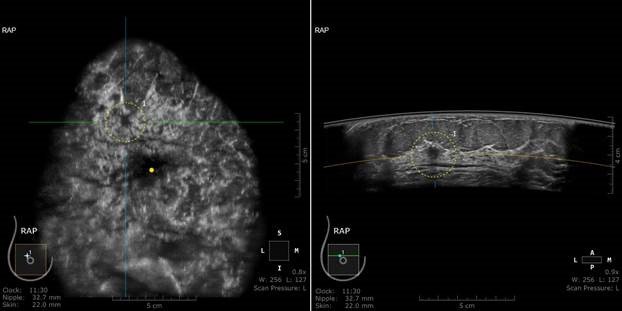

width= The ABUS exam demonstrated a .7cm lesion in the right breast. The lesion was not seen in her screening 3D mammogram, as it was likely obscured by dense breast tissue. Photo Credit: Fort Jesse Imaging's Gale Keeran Center for Women

Her doctor agrees. “ABUS looks at the breast in a different way than the screening mammogram,” says Dr. Daniel Ha, Jan’s radiologist. “In Jan’s case, the ABUS could see through the density and detect a cancer that was not seen on her 3D mammogram. Even with the best mammogram available today, 3D mammography is still challenged in high breast density. For Jan, ABUS provided a more comprehensive way to look at the breast.”